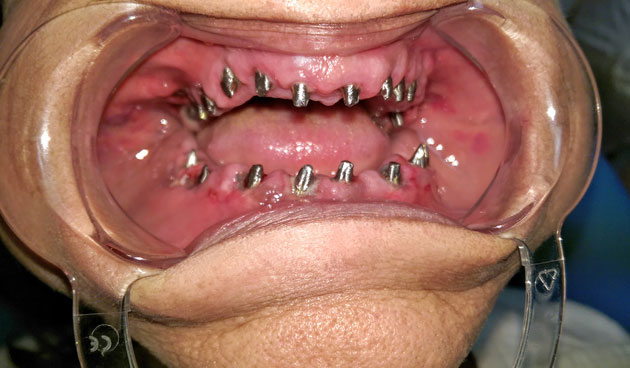

Azonnal terhelhető implantátum szájba helyezés közben

Esetbemutatók